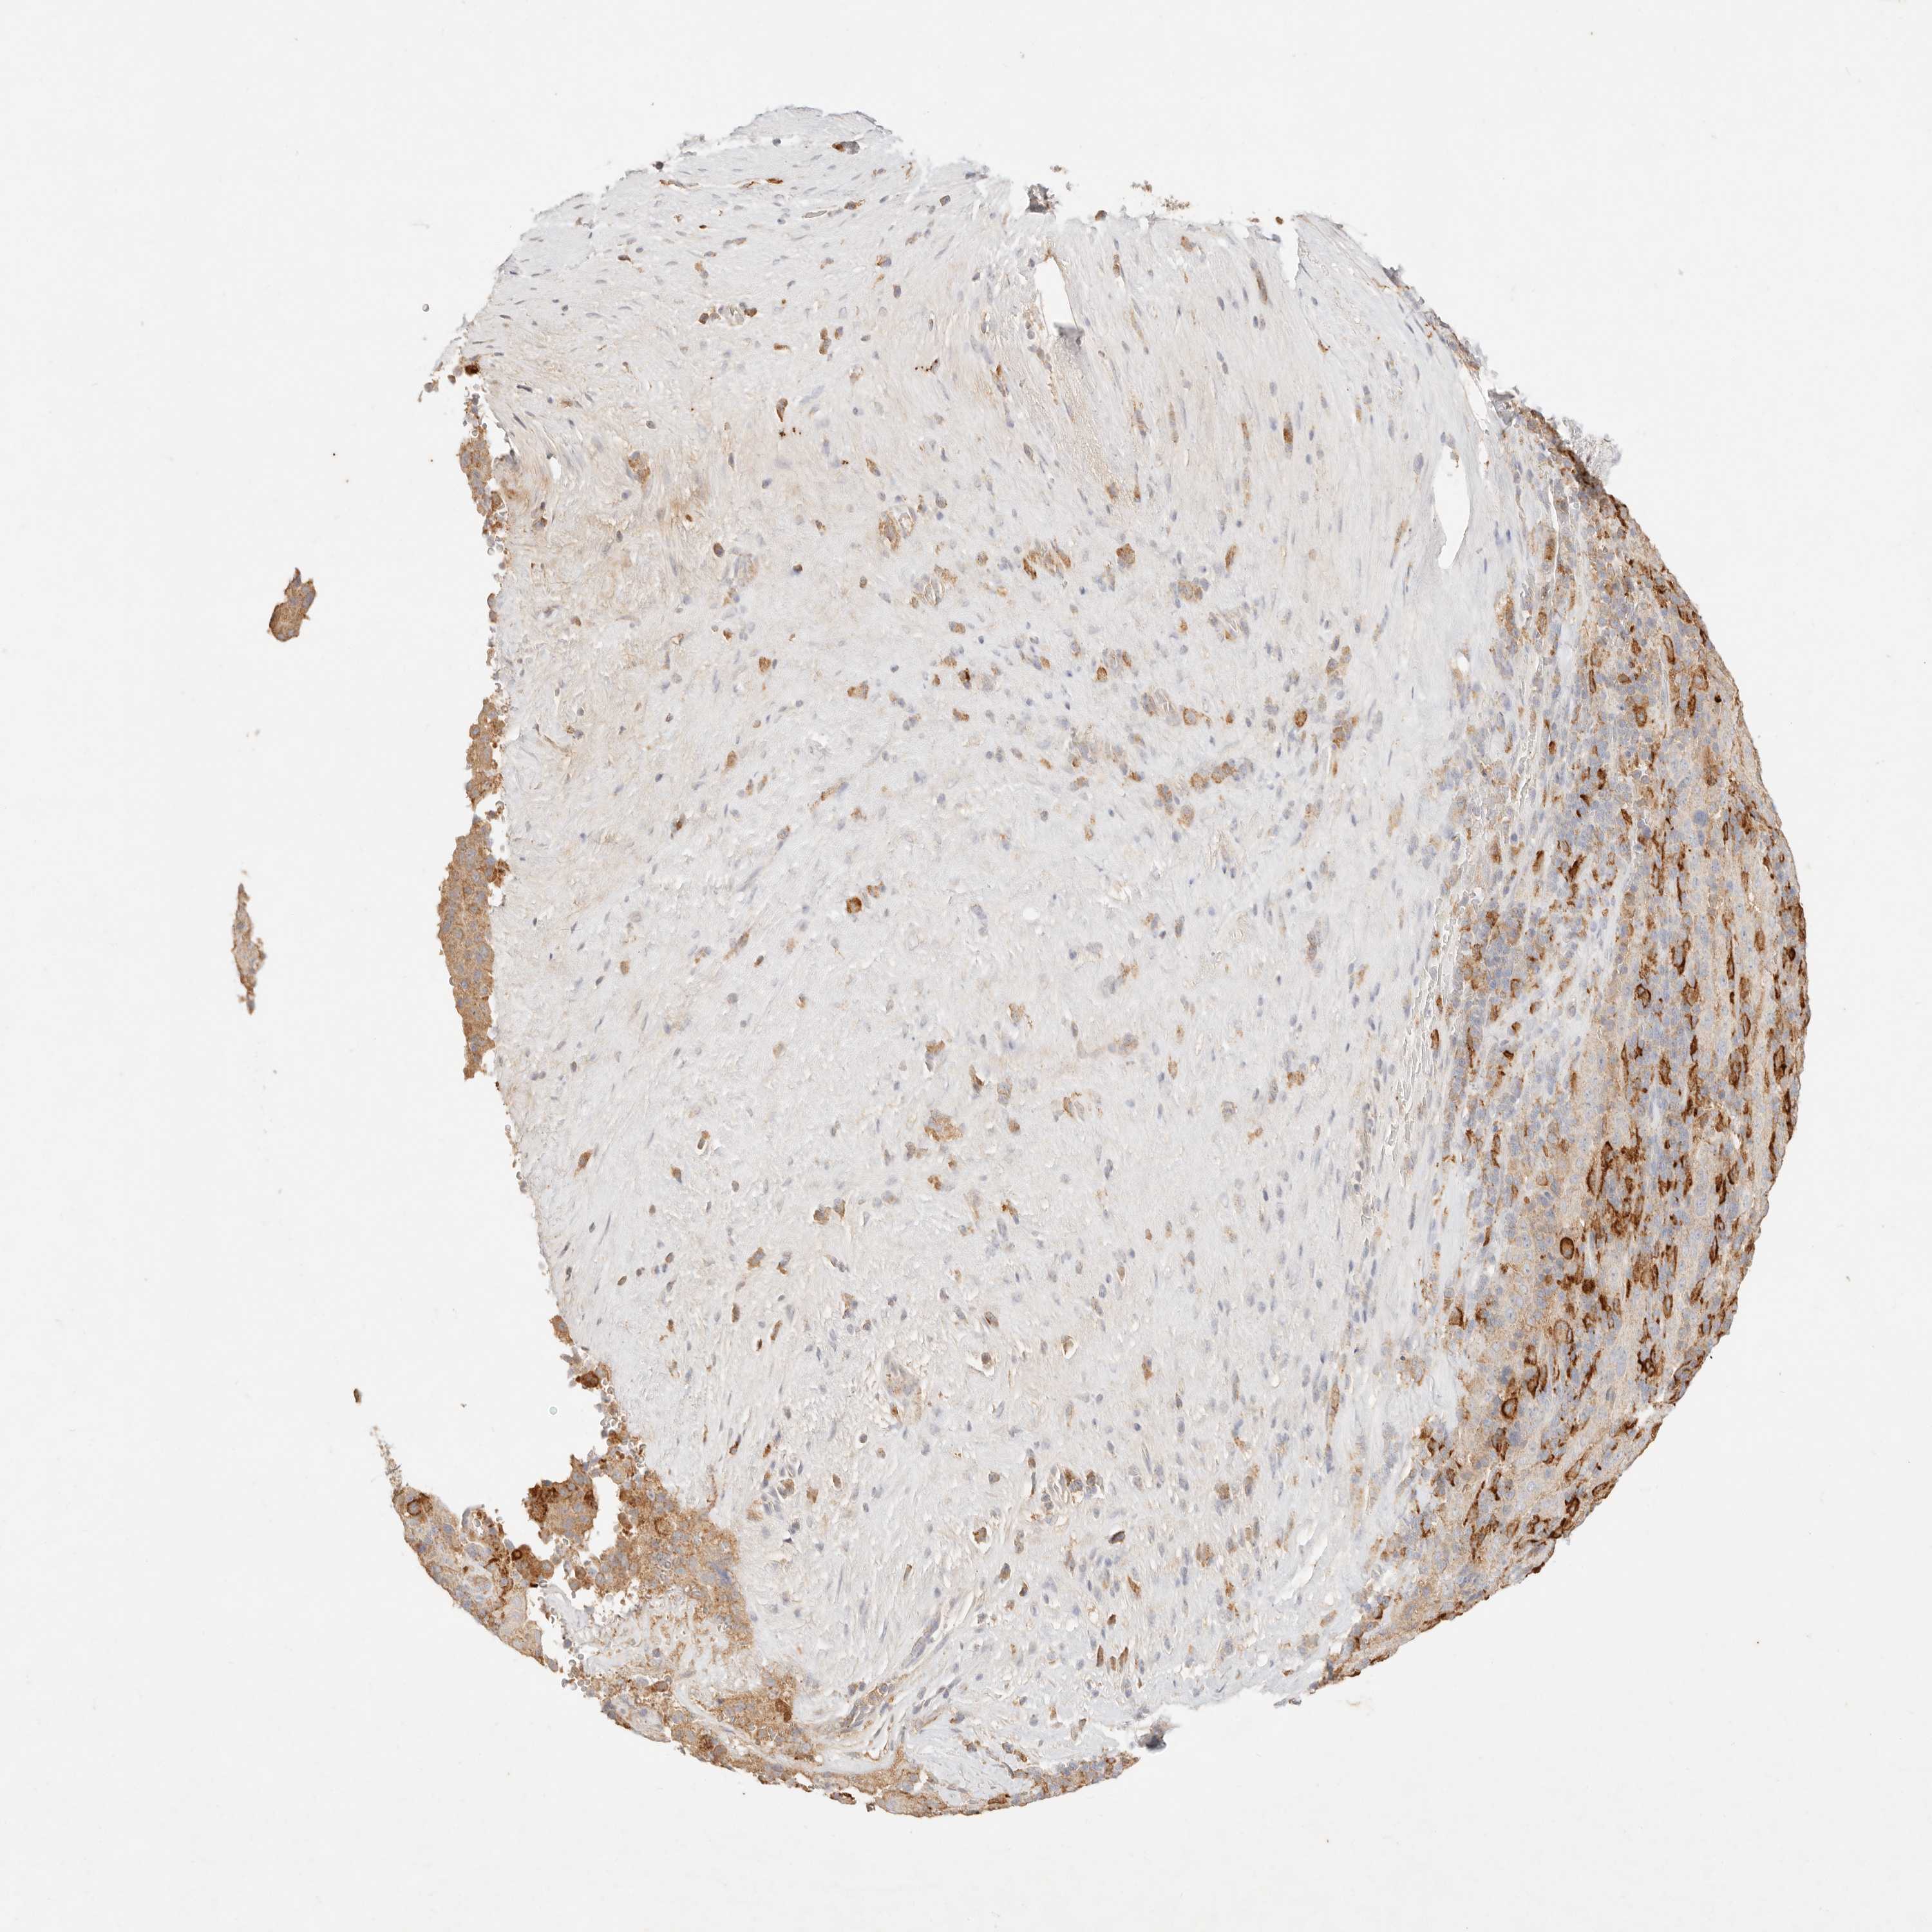

PANCREATIC CANCER - Protein expressioni

A mouse-over function shows sample information and annotation data. Click on an image to view it in a full screen mode. Samples can be filtered based on level of antibody staining by selecting one or several of the following categories: high, medium, low and not detected. The assay and annotation is described here.

Note that samples used for immunohistochemistry by the Human Protein Atlas do not correspond to samples in the TCGA dataset.

Antibody stainingi

Antibody staining in the annotated cell types in the current human tissue is reported as not detected, low, medium, or high, based on conventional immunohistochemistry profiling in selected tissues. This score is based on the combination of the staining intensity and fraction of stained cells.

Each image is clickable and will lead to virtual microscopy that enables deeper exploration of all samples and also displays staining intensity scores, fraction scores and subcellular localization as well as patient and tissue information for each sample.

Antibody HPA028587

Staining

High

Medium

Low

Not detected

Intensity

Strong

Moderate

Weak

Negative

Quantity

>75%

75%-25%

<25%

None

Location

Nuclear

Cytoplasmic/membranous

Cytoplasmic/membranous,nuclear

Adenocarcinoma, NOS